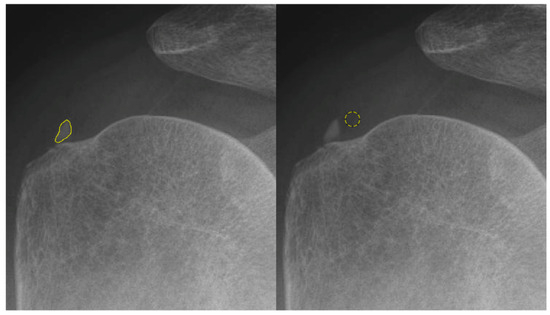

Shoulder X-rays were acquired using the INNOVISION DXII system (DK Medical Systems, Seoul, Republic of Korea), the primary imaging device used at our institution. For the analysis of the supraspinatus tendon, a 30-degree caudal tilt view was employed to optimally visualize the tendon and its footprint on the greater tubercle of the humerus. The subscapularis tendon was assessed using an axial view. To accurately capture both the calcific deposit and the normal tendon areas for grayscale value analysis and quantitative assessment, we employed ImageJ (Version 1.53, National Institutes of Health, Bethesda, MD, USA), an open-access software, to delineate the region of interest (ROI) from the collected raw radiographic images. The original Digital Imaging and Communications in Medicine (DICOM) images, with a pixel spacing of 1.41 × 1.41 mm, obtained from the Picture Archiving and Communication System (PACS) were imported into ImageJ. The pixel brightness intensity values were represented in an 8-bit image. Subsequent grayscale analysis was executed using ImageJ’s default settings, without the application of thresholding or Gaussian blur. Histogram analysis was conducted with 256 bins, and pixel intensities were normalized to a range of 0–255. The ROI was meticulously defined to encompass the calcific deposit area, with careful attention given by a physician. Additionally, a circular ROI was marked on the adjacent tendon tissue located proximal to the calcific deposit, situated between the hypoechoic bursa overlying the tendon and the cortex of the humeral head (Figure 1).

Figure 1.

A 59-year-old male patient with calcification on the right supraspinatus. A 30-degree caudal tilting view of right shoulder. Region of interest 1 (yellow outline) was created with a freehand selectionalong the contour of the calcification (left). Region of interest 2 (yellow circle) was selected with a radius of 20 pixels at the normal tendon portion right next to the calcification (right).